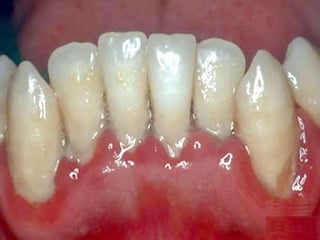

Tooth Decay (Cavities, “Caries”)

• “Processed” carbohydrates, i.e.,

sugars

• Bacterial (Strep. mutans, lactobacilli)

acidic erosion of enamel

• Role of pH, spacing, brushing, Fl

• Tartarplaquecalculus =

bacteria, proteins, cells

Periodontal Disease

• Bacteria

–Actinobacillus

–Porphyromonas

–Prevotella

• Gingiva, periodontal ligaments,

bone, cementum